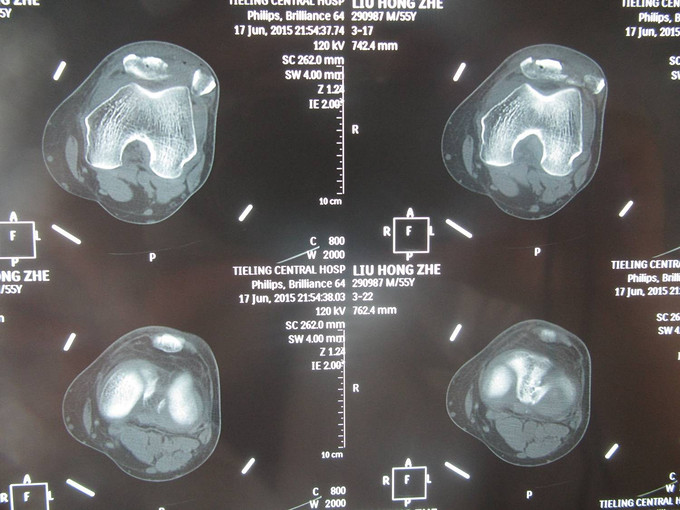

患者自诉于2015年5月17日晚21点多在外不慎摔伤,致左膝部疼痛肿胀活动受限,当时无意识不清,急诊送当地医院(铁岭市中心医院),行左膝关节DR及三维CT:左髌骨骨折。今为进一步治疗急于我院中国医科大学附属盛京医院,行X线片检查示:左髌骨骨折,急诊以“左髌骨骨折”为诊断收住入院。

诊断:左髌骨骨折 患者入院后左膝部抬高,冷疗,消肿等对症治疗后,约一周后行左髌骨骨折切开复位张力带内固定术。